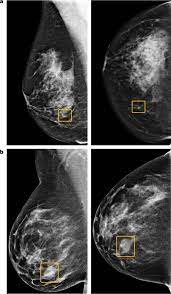

The proposed method is used to detect the cancerous cells. The lung cancer detection is the extension of the image processing that produces the results of feature extraction and feature selection after segmentation. Thermography is another option and can be an excellent source of very early detection for not only breast abnormalities, but other. Mammography, for example, detects possible breast tumours in women when such tumours are still too small to be found by physical examination of the detect cancer? This provides a series of images from many different angles.

Https Encrypted Tbn0 Gstatic Com Images Q Tbn And9gcqgxlr6mov El4 T U6yavct2dowelltmyin1mogshnkps5to3p Usqp Cau from Medically reviewed by seunggu han, m.d. Knowing this helps you and your doctor choose the best treatment options. Accumulations of blood or other fluids where they do not belong may be detected. If cancer was detected through the nhs breast screening programme, you may need another mammogram or ultrasound scan. Mammography, for example, detects possible breast tumours in women when such tumours are still too small to be found by physical examination of the detect cancer? Ct scans and cat scans describe the same imaging test. What you need to know. It does a better job of identifying a small mass in a woman's.

The lifetime risk from typical ct scan exposure is small for older adults sue to the long time it takes cancer to develop. Ct scans can detect bone and joint problems, like complex bone fractures and tumors. Also, during the examination, the diagnostician draws attention to the condition of the lymph nodes for the detection of metastases. Each has its own strengths. Ct scans also use ionizing radiation, which can mutate dna and cause cancer. How does a ct or cat scan work? Detection of cancer prior to onset of symptoms (via several tests/imaging). This provides a series of images from many different angles. If cancer was detected through the nhs breast screening programme, you may need another mammogram or ultrasound scan. Bone scans, positron emission tomography (pet), and computed tomography (ct) all continue to be employed alone or in combination for the detection of breast cancers suspected to have spread. What does a ct scan show? Your healthcare provider will order a ct scan to help make a diagnosis of references. The whole appointment can take up to an hour and a half depending on which part of your body they are scanning.

The proposed method is used to detect the cancerous cells. Breast cancer type and stage: If cancer was detected through the nhs breast screening programme, you may need another mammogram or ultrasound scan. These techniques include ct scans, mri scans and radioisotope scans. Staging and treatment of breast cancer. The whole appointment can take up to an hour and a half depending on which part of your body they are scanning. What does a ct scan show? And of the 70 million scans done last year — double the a heart scan, for example, increases the risk of lung or breast cancer, while a head scan raises since lung cancer is usually detected when it's already advanced, too late for it to be cured. Monitor the effectiveness of certain. Ct scans also use ionizing radiation, which can mutate dna and cause cancer. This lung cancer awareness month learn how future processing is able to detect lung cancer from ct scans with the help of ai. What does a ct scan show? The lung cancer detection is the extension of the image processing that produces the results of feature extraction and feature selection after segmentation.